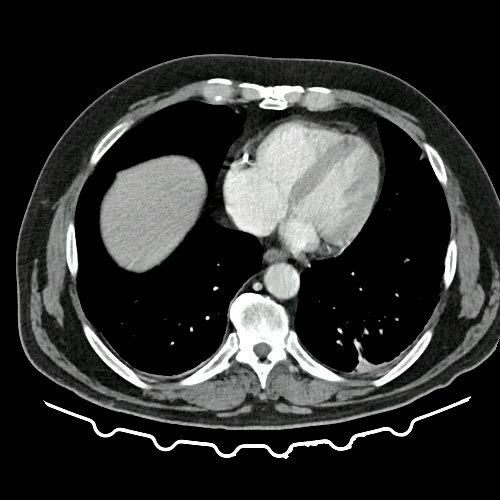

• TAC de tórax con contraste EV (Día 10): La porción visualizada de la glándula tiroides es de características normales. Las estructuras vasculares supraaórticas son de características normales, permeables. La aorta ascendente, el cayado y la aorta descendente son de calibre y trayecto conservados, permeables. Las estructuras venosas mediastinales: vena cava superior, vena cava inferior, venas pulmonares superiores e inferiores y venas ácigo-hemiácigos, son de calibre y trayecto conservado, permeables. Vena ácigos prominente. La arteria pulmonar y sus ramas son de calibre y trayecto conservados, permeables. Relación aórtico-pulmonar conservada. El corazón es de tamaño normal. El pericardio es de espesor conservado. El esófago es de calibre y trayecto normales. El mediastino está en posición central. No se observan adenomegalias mediastinales, axilares o hiliares. El árbol traqueobronquial no presenta alteraciones. Aisladas atelectasias laminares en ambos lóbulos inferiores y en segmento lingular inferior. No se observa engrosamiento o derrame pleural. Marcados cambios osteoartrósicos de la columna dorsal.

TAC de tórax, abdomen y pelvis con contraste EV (Día 10) Corte axial